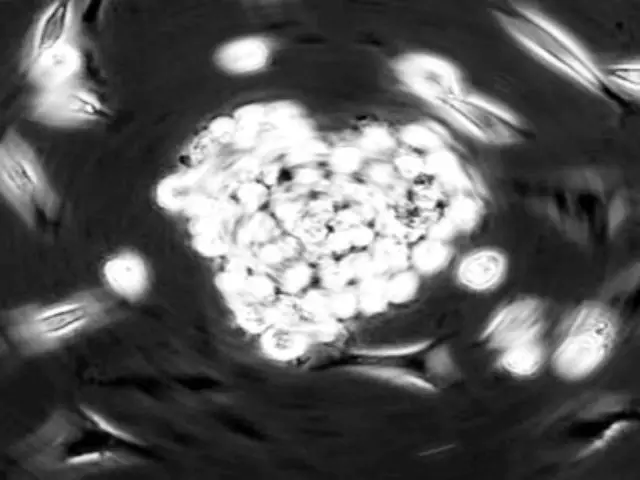

萨斯曼说:“细胞衰老和致癌风险之间有一个危险的平衡。”如果利用生物技术来走这根危险的平衡木,那会怎样?利用有癌变倾向的细胞的超强增生和生存的能力让心脏祖细胞恢复青春活力。心脏祖细胞是一类罕见的干细胞,会不定期地复制新的心脏细胞。能否让这种细胞再次分裂而不形成肿瘤呢?这正是萨斯曼研究小组的目标之一。

萨斯曼和同事在今年5月29日出版的《生物化学》杂志上发表论文称,他们探索了如何利用一种名为Pim的酶。已知这种酶与特定类型的癌细胞生长有关,他们在小鼠的心脏祖细胞中过度表达Pim,结果发现,在健康细胞中,Pim有助于促进染色体分裂,染色体分裂是细胞分裂过程中的关键一步。

这正是萨斯曼小组所做的研究。他们修改了小鼠的心脏祖细胞,使其能在细胞内特定位置过度表达PIM1基因。他们用更多的关键Pim酶瞄准这些特定位置,希望这样能帮助心脏抵抗衰老。这确实起了作用。与对照组相比,过度表达PIM1基因的小鼠活得更长,并表现出更强的细胞增生能力。而且有趣的是,根据细胞内基因被过度表达的位置不同,所产生的作用效果是不同的。

萨斯曼和同事在人体组织中也重复了这一试验,组织样本来自心脏病患者,靠心室辅助装置泵血维持生存。目前,研究小组正在努力争取资金以进行人体临床实验,他们会采集病人自身的心脏祖细胞,修改它们以过度表达PIM1基因,然后再放回病人心脏,希望这些细胞能恢复活力,并刺激其心脏组织修复自身。